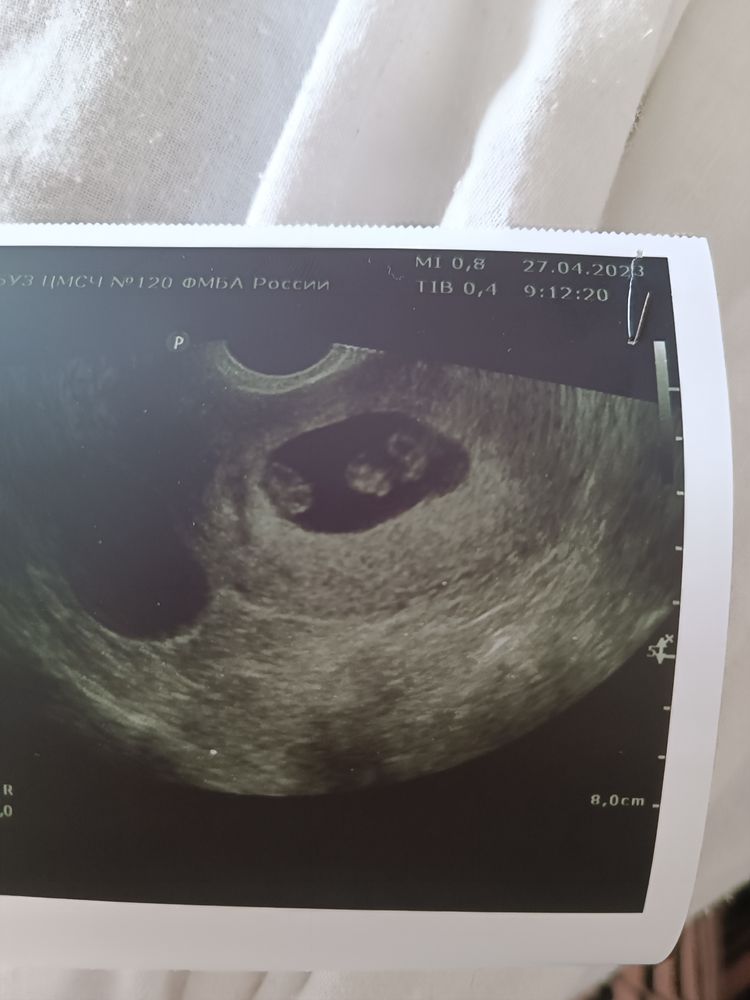

7,2 недели